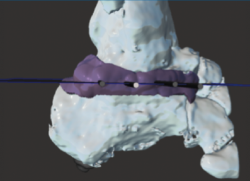

Se trata de un caso del Dr. Cuervas-Mons, publicado en Techniques in Orthopedics(15), acerca de un paciente varón de 54 años que acude a la consulta con dolor del retropié y deformidad en varo. Tras la valoración, se evidencia pseudoartrosis sintomática (Figura 9), por lo que se decide llevar a cabo tratamiento quirúrgico.

Se presenta un problema: la identificación del plano de pseudoartrosis es fácil de manera preoperatoria con el uso de imágenes; sin embargo, la identificación del plano de pseudoartrosis completo de manera intraoperatoria puede ser difícil, siendo necesario una resección ósea amplia y en ocasiones insuficiente.

Utilidad de la impresión 3D: se decidió imprimir una guía 3D de corte como ayuda intraoperatoria. La guía permite la resección de la coalición de manera completa y reducir la necesidad de guía con fluoroscopia.

- Obtención de las imágenes (Figura 10).

- Identificación del plano de pseudoartrosis (Figura 11).

- Diseño de la guía de corte guiada por aguja de Kirschner (Figura 12).